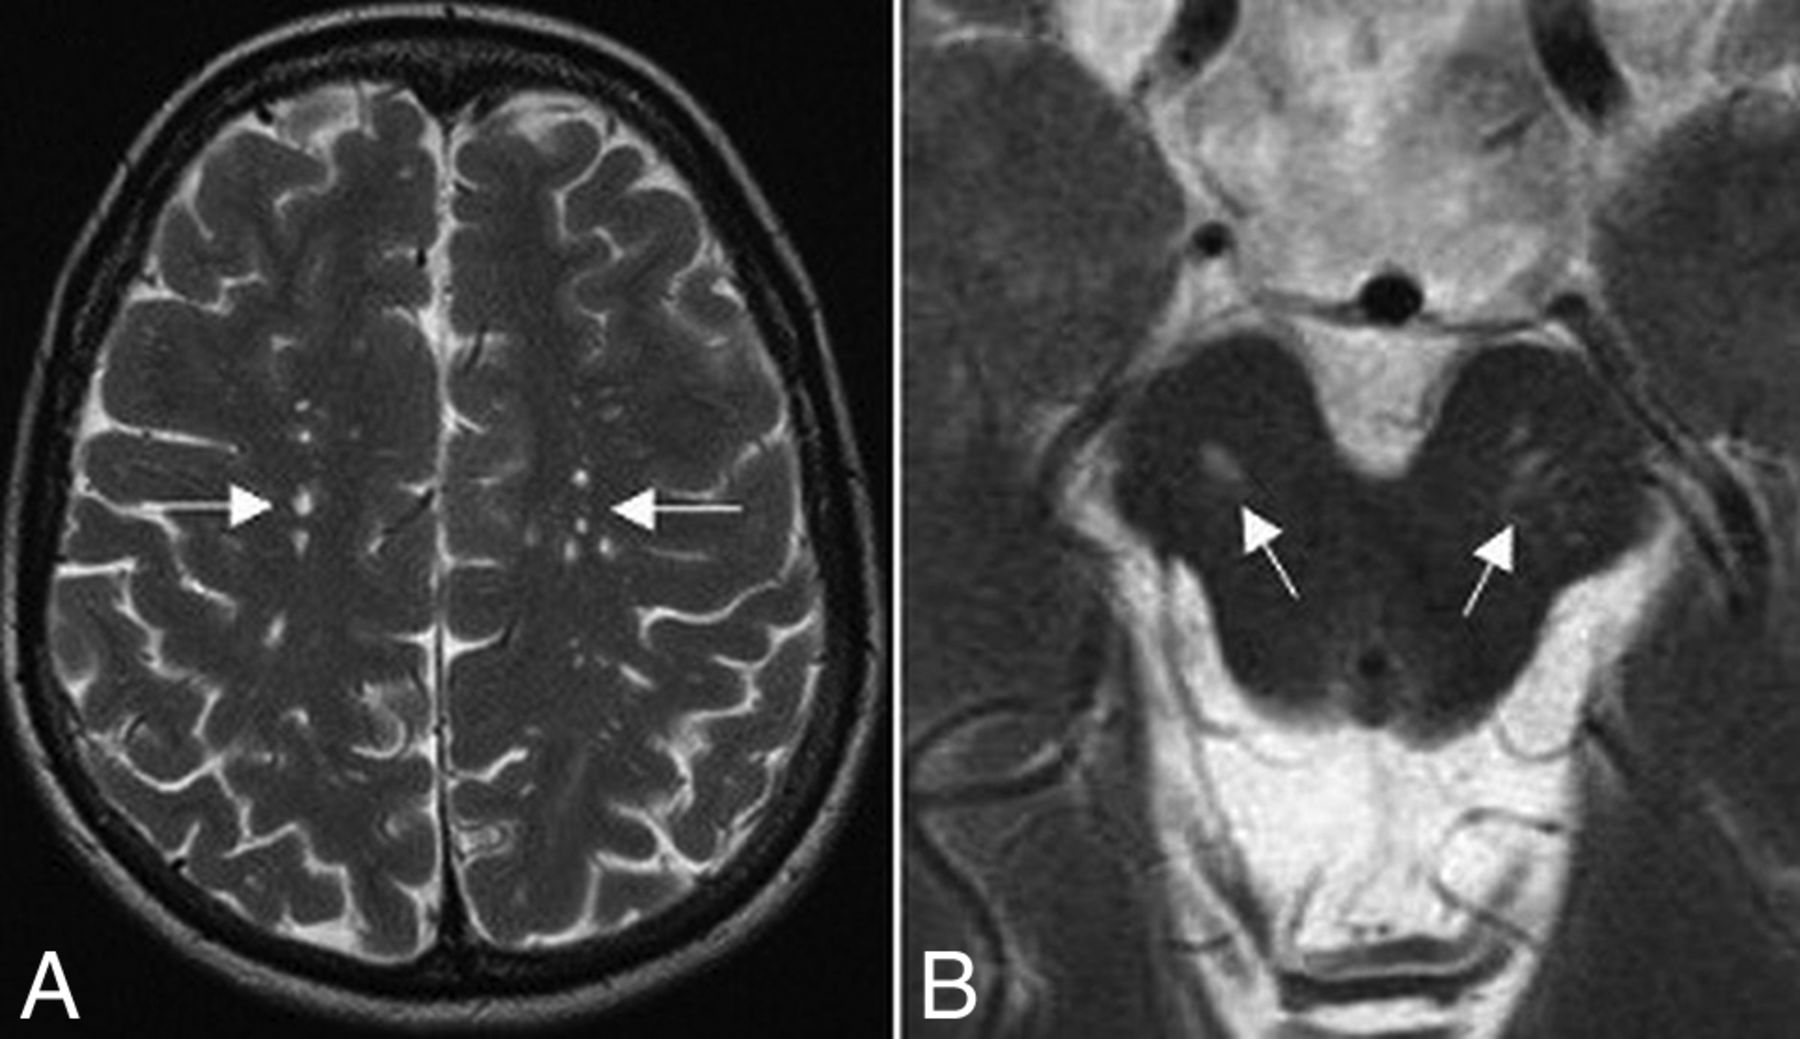

A partially empty sella and a small pituitary gland were seen in 20 patients (76.9%); they were the most common MR imaging abnormalities in our cohort (Fig 1). Patients with WSS had a significantly smaller mean pituitary gland volume of 173 ± 91 mm3 compared with healthy control subjects with a mean of 480 ± 85 mm3 (P < .005). Six patients (23%) had normal pituitary gland volume. The pituitary stalk varied in size, but most of the affected individuals had a relatively small stalk. No abnormal suprasellar and parasellar structures were noted.

Sagittal T1-weighted MR imaging for patient 22 shows a partially empty sella and a small pituitary gland (arrow).

Axial T2 images show type I (A) and type III (B) prominent perivascular spaces.